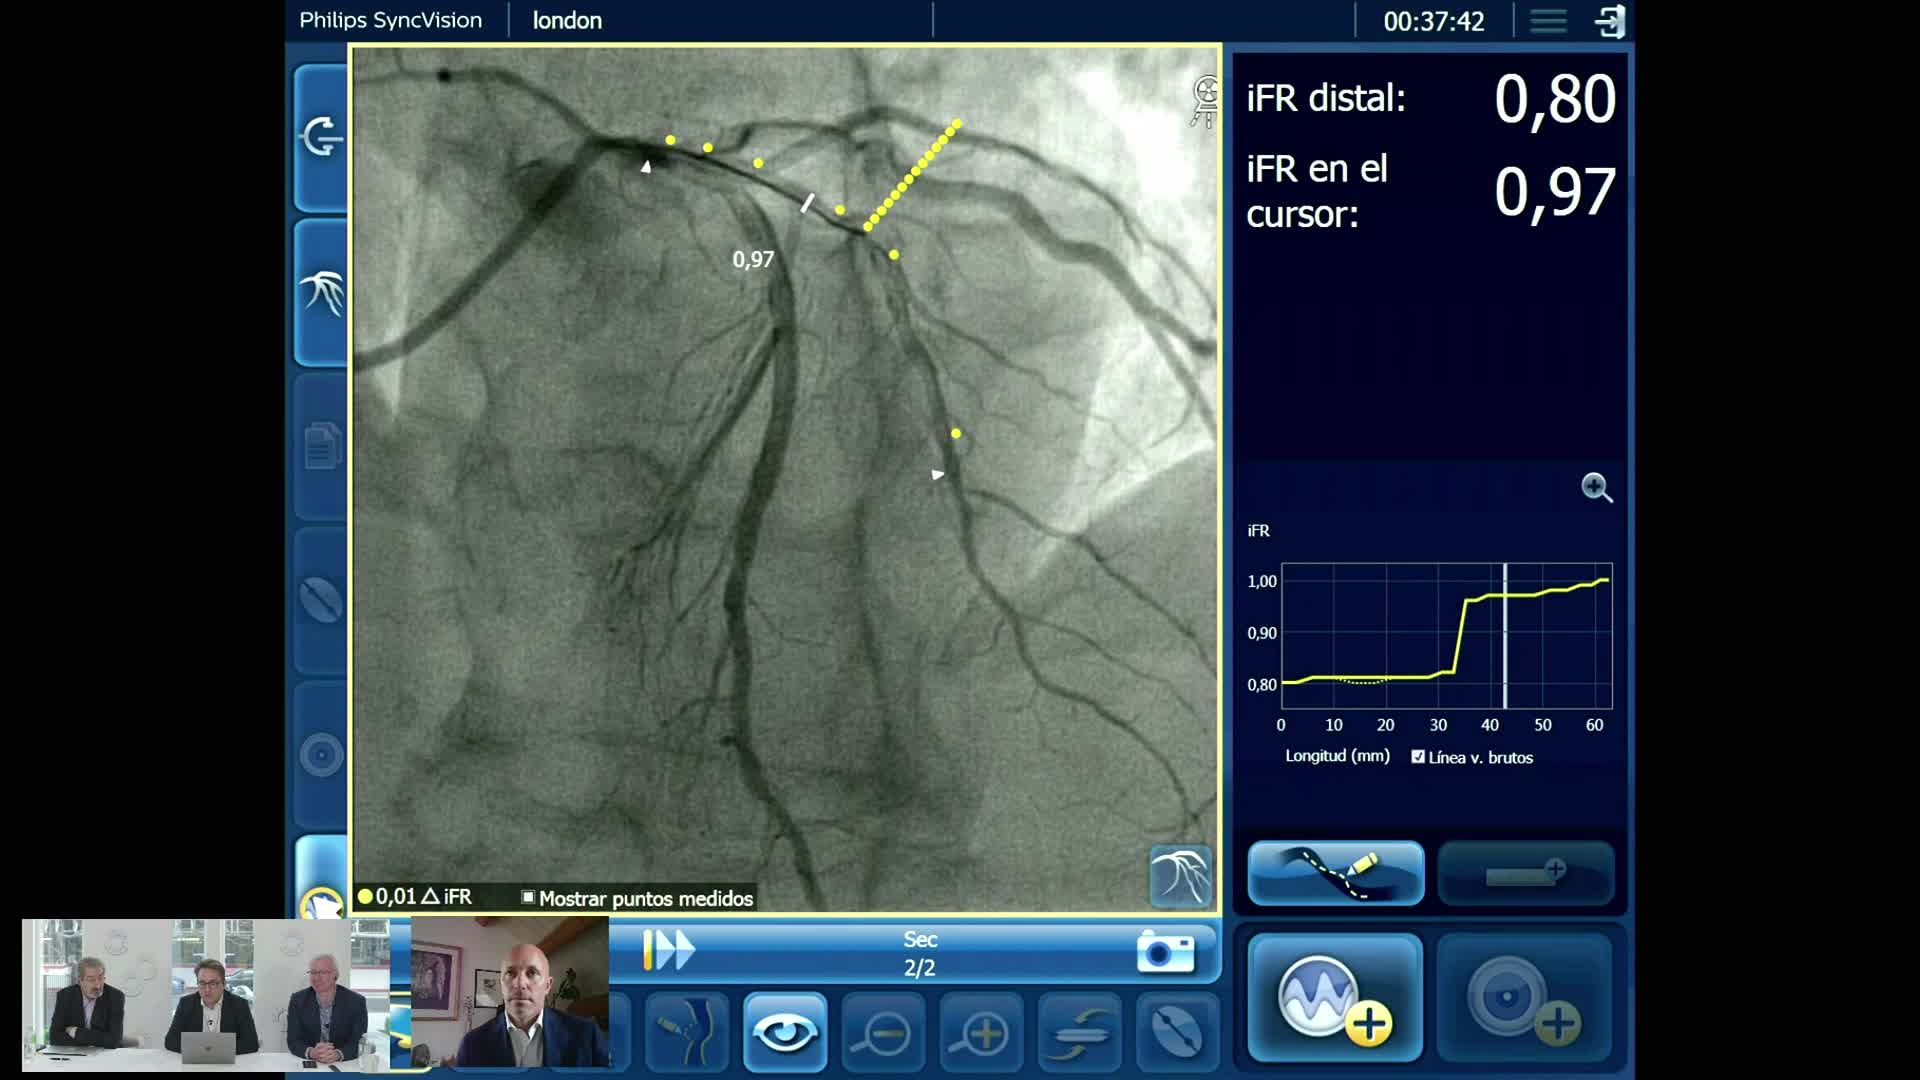

Using SyncVision Co-registration to distinguish between focal and diffuse coronary disease. - Prof Giuseppe Tarantini

Essential steps for physiology-based PCI planning and guidance - Dr Allen Jeremias

Understanding how SyncVision differs from other co-registration based technologies - Dr Justin Davies